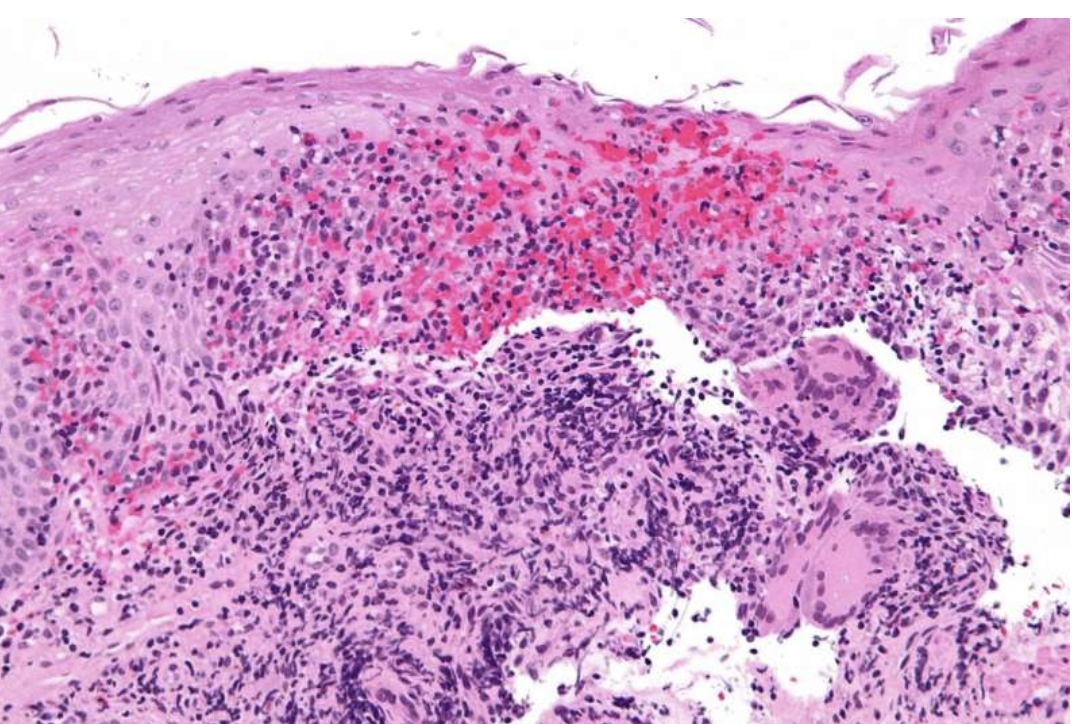

首先,停药可能导致克罗恩病的复发或加重。这是因为克罗恩类克等药物能够有效地抑制炎症,控制病情。一旦停药,炎症可能重新活跃,引发腹泻、腹痛、疲劳等症状。因此,患者在停药前应该咨询医生,制定合适的停药计划,并密切观察病情变化。